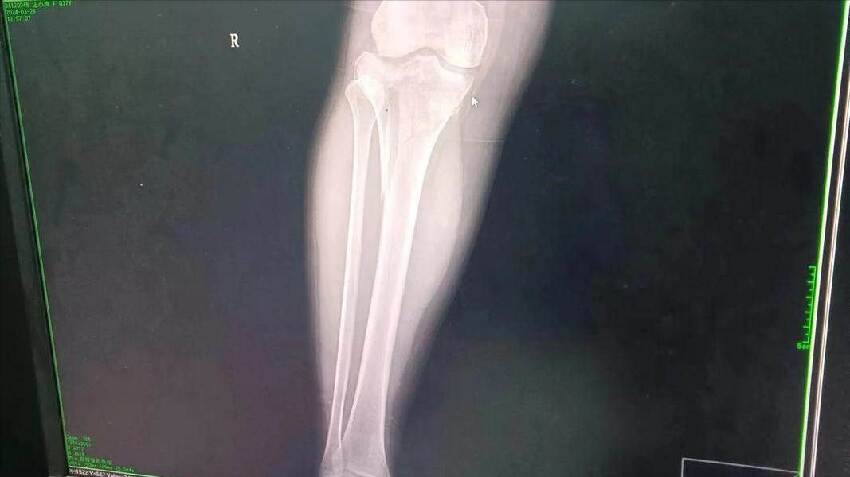

她是滑倒后造成股骨頸骨折,屬於中年人較為常見的損傷類型。

醫生團隊評估后,安排了常規的內固定手術。

手術順利完成,術中生命體征平穩,術后也沒有特殊並發癥徵兆。